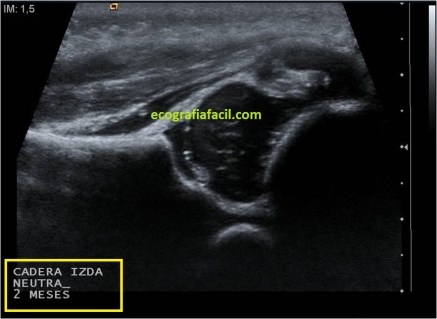

Para terminar solo me queda mostrarte como se ve una exploración normal y otra patológica:

Las imágenes hablan por si mismas, la perfecta correlación de estructuras en la armónica normalidad y la ausencia de ángulo entre iliaco y acetábulo en la patológica…

The images speak for themselves, the perfect correlation of structures in harmonic normality and the absence of angle between iliac and acetabulum in the pathological .